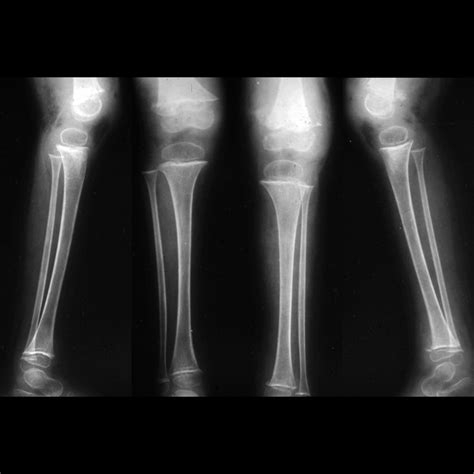

• X-rays: Often the first line of defense for bone fractures or lung issues.

X-ray Minimal Bone fractures, pneumonia, chest congestion